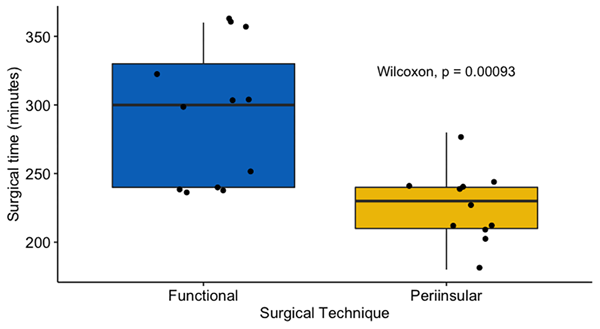

Al comparar las 2 técnicas, se encontró que la HF tuvo una duración quirúrgica estadísticamente mayor (5 ± 1,5 vs 3,83 ± 0,5 horas; p = <0,001) (Figura 6). No hubo diferencia entre los pacientes que se sometieron a HF y los que recibieron HPI en la duración de la estancia en la Unidad de Cuidados Intensivos (4,5 ± 5 frente a 6 ± 3,5 días; p = 0,23) y la estancia hospitalaria total (13,5 ± 10 frente a 16 ± 4,5 días; p = 0,138). En el último seguimiento, no hubo diferencia en el número de pacientes con resultados Engel Clase I obtenidos después de la última operación (HF: 66,7 %, HPI: 90,9 %; p = 0,724). Dos pacientes del grupo de HF (16%) requirieron re-operación luego de un pobre control de crisis posterior a la cirugía. No se necesitaron reoperaciones en el grupo HPI para mejorar el resultado de Engel (Tabla 2).

Figura 6. Duración quirúrgica. Se encontró que la HF tiene una duración quirúrgica estadísticamente más larga que los pacientes que se sometieron a una HPI modificada. (5 ± 1,5 vs 3,83 ± 0,5 horas; p = <0,001).